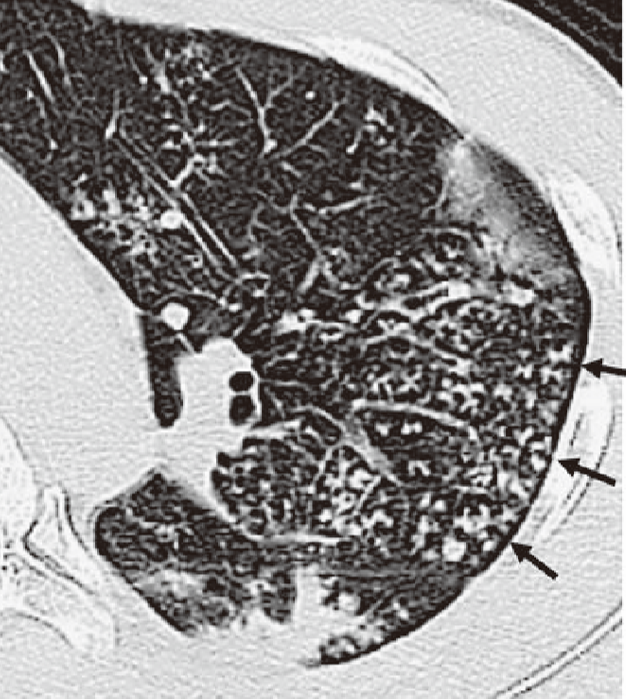

Causes and Imaging Patterns of TreeinBud Opacities CHEST Tree Bud Appearance 220 rows when peripheral areas of lung are opacified or plugged by exudates, they cause the appearance of a v or y shaped branching tree. These small, clustered, branching, and nodular opacities represent terminal airway mucous impaction with. It consists of small centrilobular. Tree Bud Appearance.

TreeinBud Pattern at ThinSection CT of the Lungs Radiologic Tree Bud Appearance It consists of small centrilobular. These small, clustered, branching, and nodular opacities represent terminal airway mucous impaction with. 220 rows when peripheral areas of lung are opacified or plugged by exudates, they cause the appearance of a v or y shaped branching tree. Tree Bud Appearance.

Treeinbud appearance Image Tree Bud Appearance 220 rows when peripheral areas of lung are opacified or plugged by exudates, they cause the appearance of a v or y shaped branching tree. These small, clustered, branching, and nodular opacities represent terminal airway mucous impaction with. It consists of small centrilobular. Tree Bud Appearance.

Tree in bud appearance Image Tree Bud Appearance 220 rows when peripheral areas of lung are opacified or plugged by exudates, they cause the appearance of a v or y shaped branching tree. These small, clustered, branching, and nodular opacities represent terminal airway mucous impaction with. It consists of small centrilobular. Tree Bud Appearance.